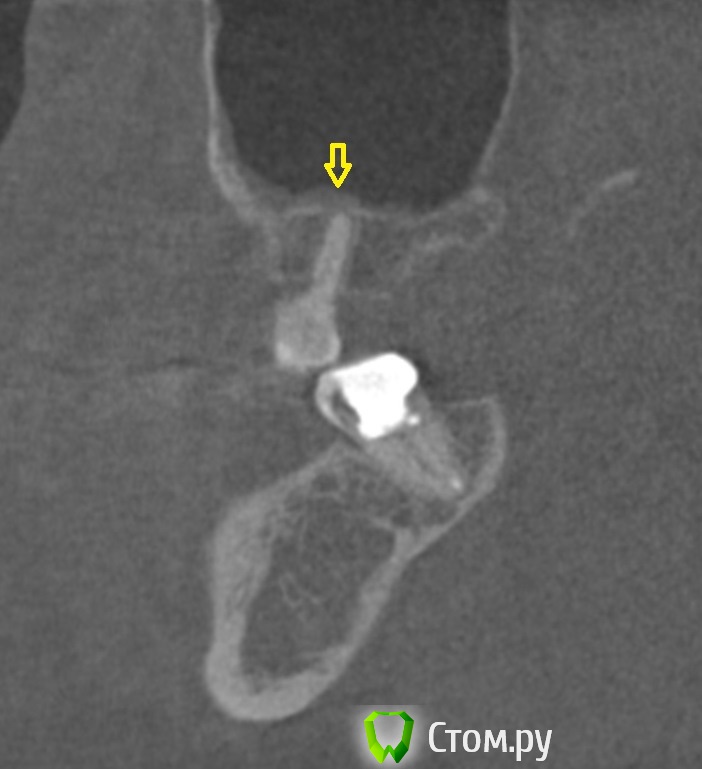

dr-krasnov Опубликовано 10 июня, 2014 Поделиться Опубликовано 10 июня, 2014 (изменено) Тэкс, посмотрел КТ. Претензий к лечению зуба не имею. 4й канал найти не удалось. То был ограниченный артефакт от запломбированного канала. Связи между этим зубом и реакцией слизистой скорее всего нет. Да и синусита нет. Изменения слизистой скорее имеют гиперпластическую природу. Источником исходных реакций послужили уже отсутствующие зубы. Архивные снимки расставили бы все точки над и. Несколько картинок: Небный на осях, можно придраться к незначительному расширению периодонтального пространства апикально, но я бы не стал http://s018.radikal.ru/i515/1406/b8/d712dd4f6158.jpg Дистальный щечный http://s020.radikal.ru/i710/1406/4f/990608ed482a.jpg Мезиальный щечный http://s018.radikal.ru/i518/1406/52/534d8d8534ec.jpg В общем, признаков периодонтита не вижу, рентгенологических показаний для резекции тоже.Я бы порекомендовал динамическое наблюдение. Изменено 10 июня, 2014 пользователем dr-krasnov 1 Ссылка на комментарий

dr-krasnov Опубликовано 10 июня, 2014 Поделиться Опубликовано 10 июня, 2014 Если есть сомнения - увеличивайте толщину выделенного слоя. http://s57.radikal.ru/i158/1406/ac/f4ed1bc20195.jpg А вот с 37 беда) http://i031.radikal.ru/1406/e2/2edce574a513.jpg 1 Ссылка на комментарий

DokDent Опубликовано 10 июня, 2014 Поделиться Опубликовано 10 июня, 2014 Если есть сомнения - увеличивайте толщину выделенного слоя. поняла, спасибо А вот с 37 беда) Похоже что виноват медиальный корень? 1 Ссылка на комментарий

dr-krasnov Опубликовано 10 июня, 2014 Поделиться Опубликовано 10 июня, 2014 Трудно сказать однозначно, скорее всего. Ссылка на комментарий